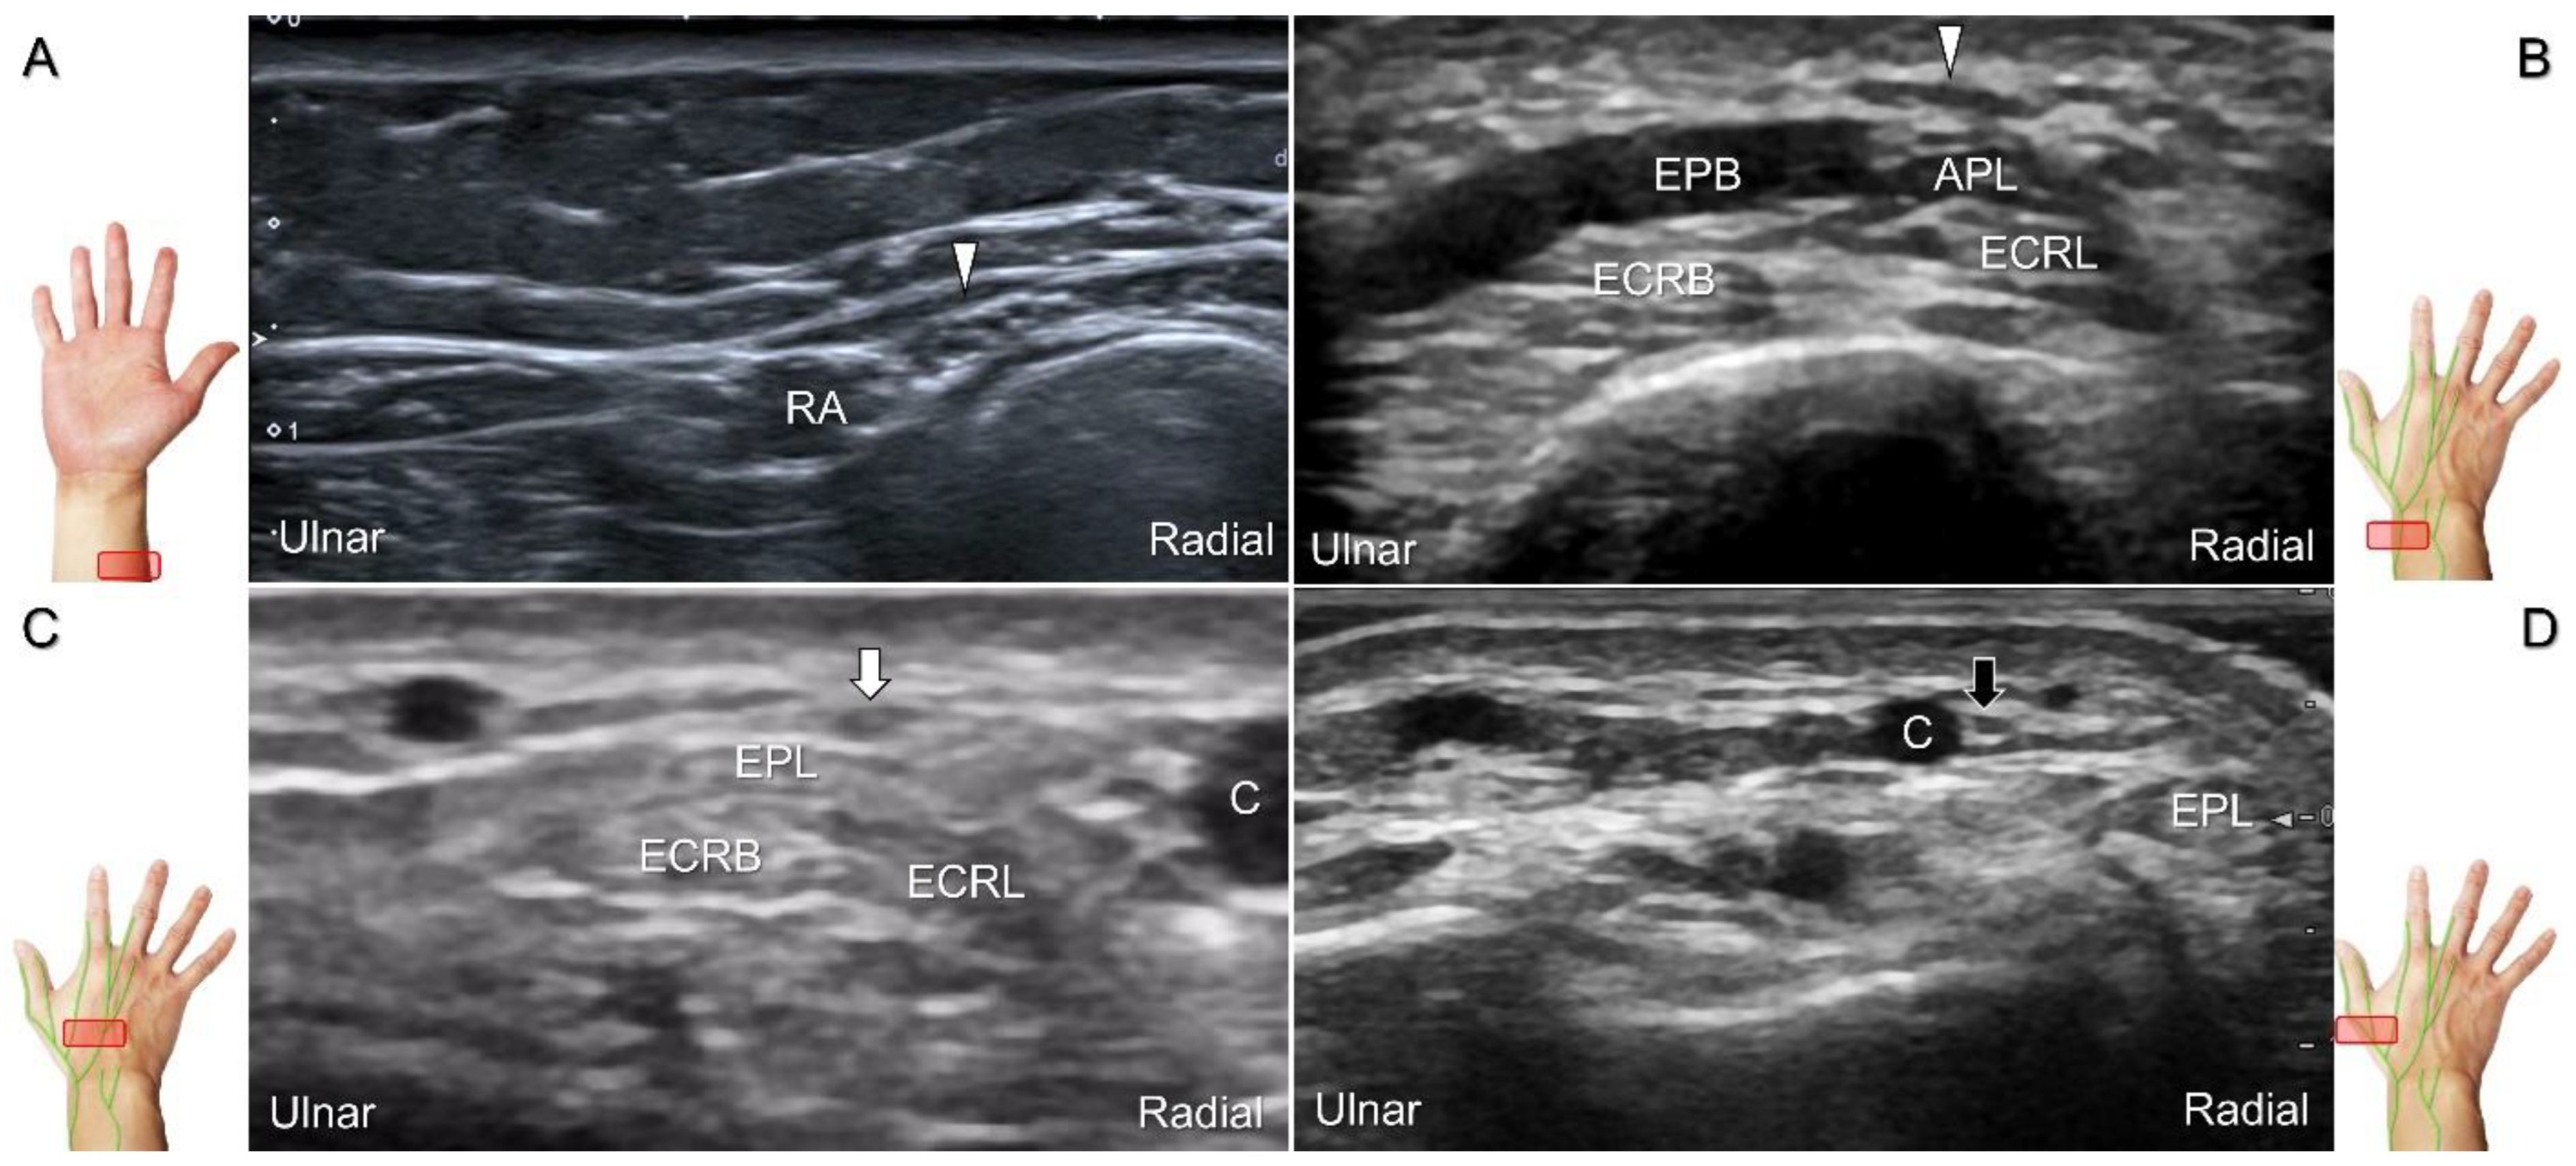

With the forearm supinated, the transducer is positioned in the axial plane at the lateral aspect of the antecubital fossa. The superficial and deep radial nerves are situated between the brachioradialis and brachialis muscles. The superficial radial nerve initially courses next to the radial artery below the brachioradialis muscle, and then departs from the radial artery in the distal third of the forearm (Figure 21A). Distally, it pierces the antebrachial fascia between the extensor carpi radialis longus and brachioradialis tendons. When tracking the terminal portion of the superficial radial nerve, the forearm can be pronated, as it courses toward the dorsal radial aspect of the wrist/hand. The superficial radial nerve travels above the proximal intersection junction between the first and second dorsal extensor compartments (Figure 21B). Later, it divides into the dorsomedial and dorsolateral branches. The former courses above the distal intersection junction of the second and third compartments (Figure 21C). The latter runs beside the extensor pollicis longus tendon (Figure 21D).

Figure 21. Sonographic imaging (short-axis view) of the superficial radial nerve from the distal third of the supinated forearm (A). With the pronated forearm, the nerve is seen to travel above the proximal intersection junction (B), divide into the dorsomedial branch coursing above the distal intersection junction (C), and the dorsolateral branch running beside the extensor pollicis longus tendon (D). Arrowheads: superficial radial nerve; white arrow: dorsomedial branch; black arrow: dorsolateral branch. RA: radial artery; APL: abductor pollicis longus tendon; EPB: extensor pollicis brevis tendon; ECRL: extensor carpi radialis longus tendon; ECRB: extensor carpi radialis brevis tendon; EPL: extensor pollicis longus tendon; C: cephalic vein.